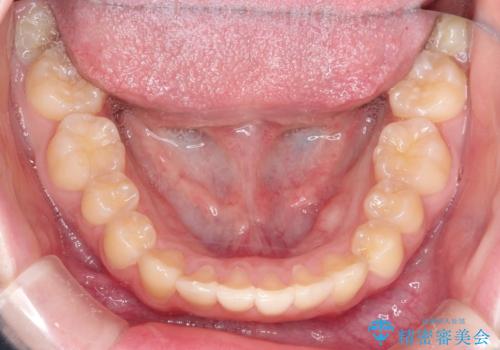

なるべく通院回数を減らして矯正したい インビザラインでのガタガタ矯正

- 10代女性

- インビザライン

- 1年2ヶ月

- 上下の歯並びを治したいとのことで来院されました。

受験生ということもあり、なるべく通院回数を減らしての矯正を希望されたので、インビザラインで治療をすることにしました。